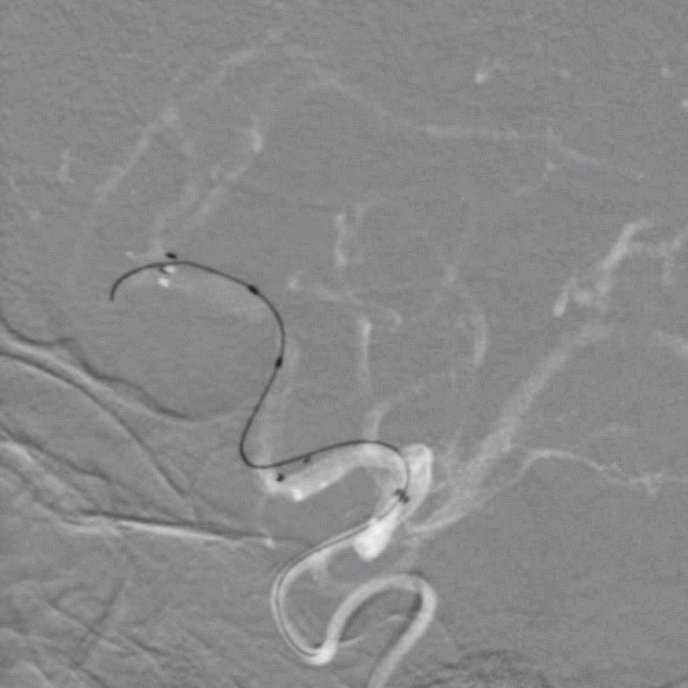

左侧颈总入路迂曲。

长鞘+125cm单弯+加硬导丝建立通路;Tethys®中间导引导管+0.014inch微导丝+10微导管。

导丝通过病变段。

微导管跟进。

确认系统位置,交换3m 0.014inch微导丝。

加奇1.75mm×9mm SacSpeed®球囊扩张导管顺利到位。

缓慢扩张。

扩张后前向血流仍较差。

重新调整入路后再次造影。

3m 微导丝配合微导管再次接近病变。

更换微导丝兼顾支撑及操纵性,协助微导管过病变段后交换3m 0.014inch微导丝。

使用SacSpeed®球囊扩张导管再次扩张。

扩张后前向血流好转。

引入3mm×21mm支架覆盖病变。

支架释放后造影。

术后3D。